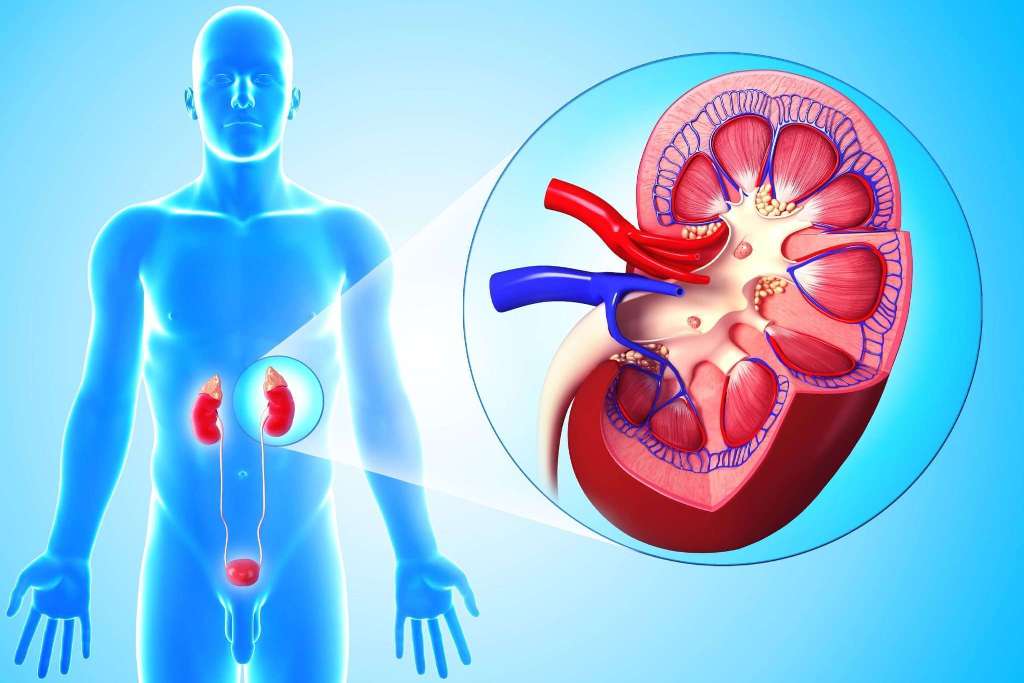

Симптомы подострого гломерулонефрита: фото и описание